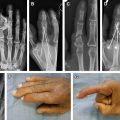

The surgical exposure to the tendons is obtained through either Bruner zigzag incisions or by the midlateral approach supported by Strickland. Midlateral incisions may provide a better bed of tissue to lie across the operative site and reduce wound tension with postoperative digital motion. Adhesiolysis should proceed from the proximal unscarred tissue to the distal scarred areas, identifying and preserving the neurovascular bundles during the process. Although Verdan suggested wide sheath excision during the tenolysis, most surgeons today recommend conservation of as much of the pulley/sheath system as possible. The tenolysis is performed with a small Beaver blade, elevator, fine tissue scissors, or specialized tenolysis instrumentation, such as a Meals tenolysis knife ( Fig. 1 ). The flexor digitorum sublimus (FDS) tendon and the flexor digitorum profundus (FDP) tendons are separated from each other, surrounding annular pulleys, and from the dorsal osseous component of the canal. Surgeons should avoid attenuating the repair site through an overaggressive tenolysis. Strickland advocates the use of a pediatric urethral sound dilator to facilitate annular pulley expansion and tendon passage through the pulley system. Patient participation to actively flex the involved digit ensures adequacy of release. A patient who is under general anesthesia or unable to cooperate with this request can have a proximal incision made in the palm or the wrist to provide access to the proximal tendon. Traction on the proximal tendon confirms the complete release of the distal adhesions. This “traction flexor check,” originally described by Whitaker, illustrates adequate flexion of the digit and signifies complete release of adhesions around the flexor tendons ( Fig. 2 ). An alternative to the traction test is the forearm compression test, where the flexors are compressed in the distal forearm that forces the released or unaffected digits into flexion.

An assessment of the quality of the pulley system and tendon itself should be addressed before skin closure. If greater than 30% of the involved tendon width has been lost or if tendon continuity is only maintained by a segment of scar (gap tissue), the tenolysis may be successful initially but may result in secondary tendon rupture during postoperative therapy. Efforts may be turned to staged reconstruction with a silicone implant if the quality of the tendon is too poor to risk rupture ( Fig. 3 ). The quality of the tendon and pulley system should be conveyed to a therapist to guide the aggressiveness of the postoperative hand therapy.